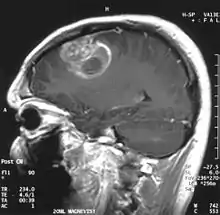

| Coronal MRI with contrast of a glioblastoma in a 15-year-old male | |

When viewed with MRI, glioblastomas often appear as ring-enhancing lesions. The appearance is not specific, however, as other lesions such as abscess, metastasis, tumefactive multiple sclerosis, and other entities may have a similar appearance.[56] Definitive diagnosis of a suspected GBM on CT or MRI requires a stereotactic biopsy or a craniotomy with tumor resection and pathologic confirmation. Because the tumor grade is based upon the most malignant portion of the tumor, biopsy or subtotal tumor resection can result in undergrading of the lesion. Imaging of tumor blood flow using perfusion MRI and measuring tumor metabolite concentration with MR spectroscopy may add diagnostic value to standard MRI in select cases by showing increased relative cerebral blood volume and increased choline peak, respectively, but pathology remains the gold standard for diagnosis and molecular characterization.